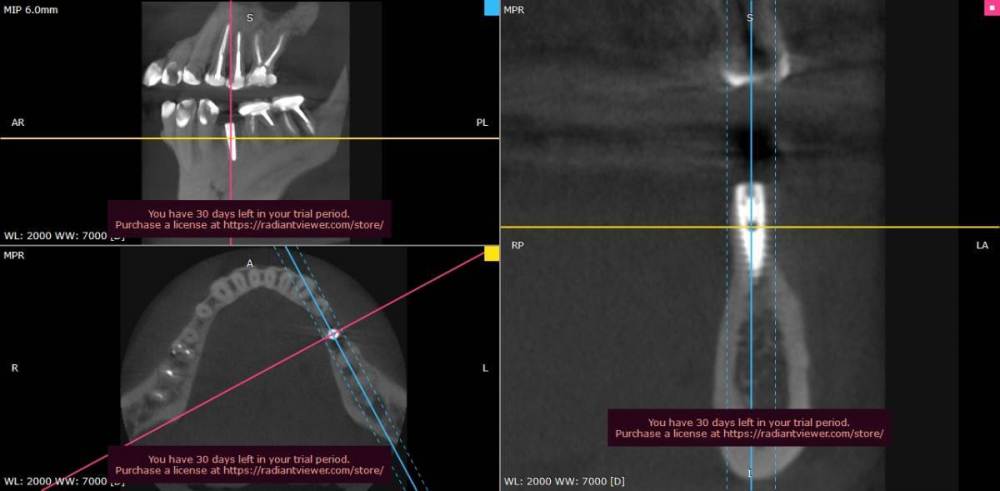

Ljocha Опубликовано 31 августа, 2022 Автор Поделиться Опубликовано 31 августа, 2022 все срезы выставлены синхронно вот так Ссылка на комментарий